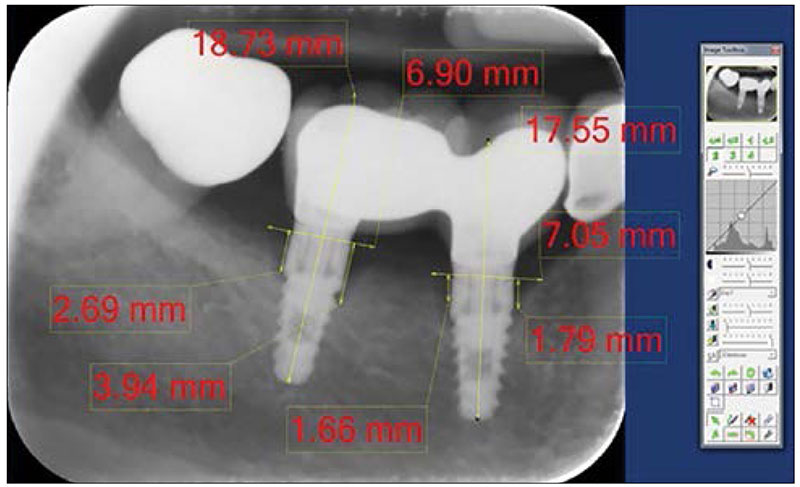

Tika veikti meziāli un distāli periimplantāta kaula augstuma mērījumi, kā atskaites punktus izmantojot implantāta un kroņa balsta (abatmenta) savienojuma vietu jeb implantāta platformu. Dubultā rentgenuzņēmuma palielinājumā tika vilkta vertikāla līnija pa implantāta garenasi un horizontāla līnija perpendikulāri garenasij caur implantāta un kroņa balsta savienojuma vietu abās implantāta pusēs. Periimplantāta kaula augstums tika noteikts kā attālums no atskaites punkta (uz horizontālās līnijas) līdz tālākajam jeb zemākajam alveolārā kaula (periimplantāta kaula) augstumam zemākajā punktā, kur saskaras alveolārais kauls ar implantāta virsmu (sk. 1. att.).

1. attēls. Ekrānuzņēmums ar periimplantāta kaula augstuma mērījumiem digitālajā periapikālajā rentgenuzņēmumā, izmantojot DIGORA® for Windows 2.5 datorprogrammu

Screenshot of periimplant bone level measurements in digital periapical radiographic image by DIGORA® for Windows 2.5 software